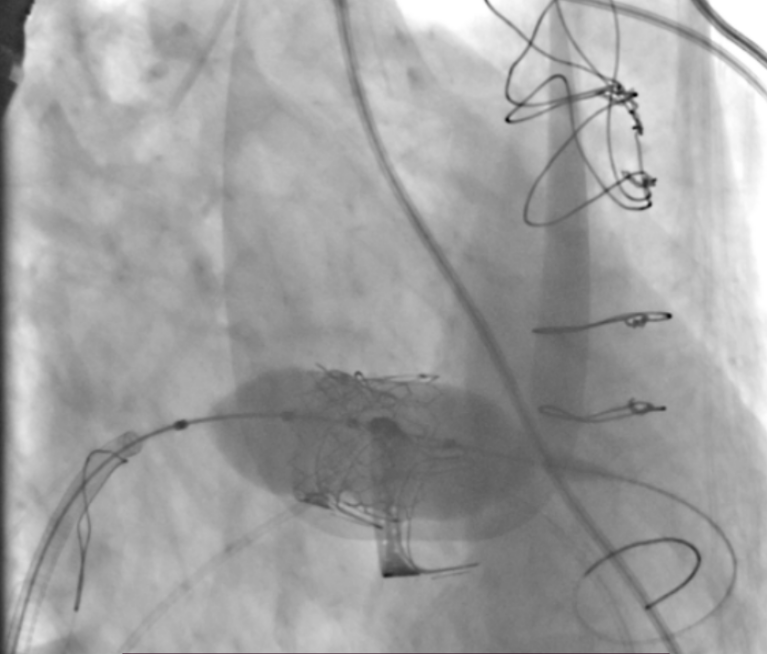

患者全麻后,穿刺右股静脉建立通路,穿刺房间隔,选用18mm球囊对房间隔进行扩张。泥鳅导丝跨二尖瓣后,根据术前评估情况,在180次/分快速心室起搏下,收缩压降至50mmHg,选用26mm Prizvalve®球扩瓣进行植入。瓣膜定位精准,释放顺利,撤出输送系统。随后,在圈套器的辅助下,导丝跨过三尖瓣,根据术前评估情况,选用29mm Prizvalve®球扩瓣进行植入。手术顺利完成。

二尖瓣球扩瓣释放

三尖瓣球扩瓣释放